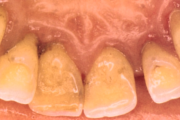

- igemepiir on taandunud (3)

- puudulik suuhügieen (5)

- igemepealne hambakivi (5)

- hammaste tundlikkus (9)

- halb hingeõhk / suu haiseb (12)